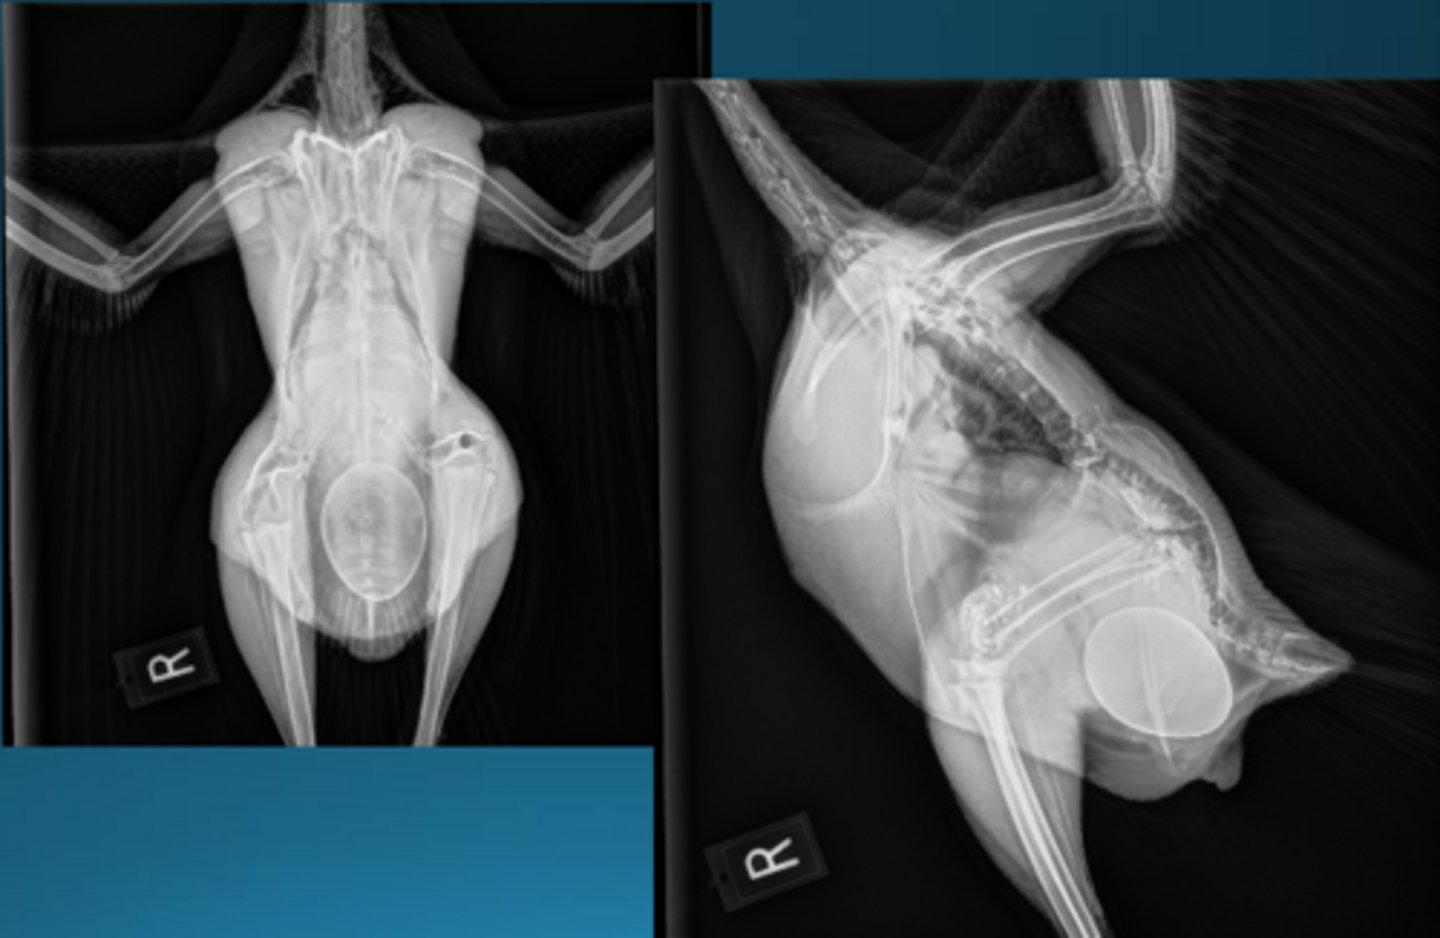

1. number of eggs

2. position = want pointy end facing south

3. shell quality = there is not a "ghost shell" meaning no hypocalcemia in this bird, margin smooth and appropriate

4. bone quality of mother = polyostotic hyperostosis, bird is taking Ca from bones and putting into egg under influence of estrogen (normal to a point)

THIS BIRD IS NOT EGG BOUND

What are some factors you want to look at on radiographs to determine if the bird is eggbound?